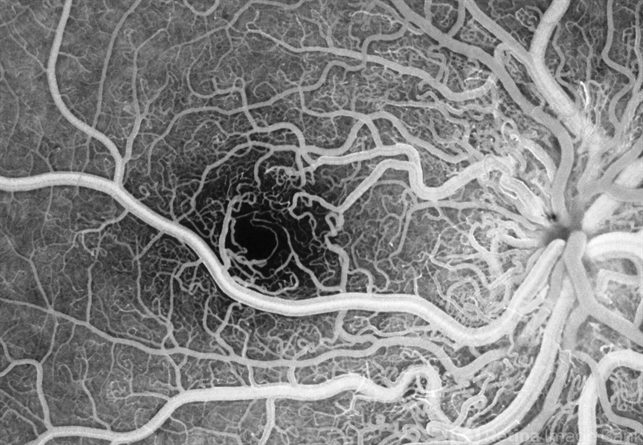

- Wyburn-Mason, retinal arteriovenous malformations, racemose hemangioma

- A 7-year-old Portuguese girl with unilateral retinal arteriovenous malformations composed of dilated, tortuous vessels with normal vision.